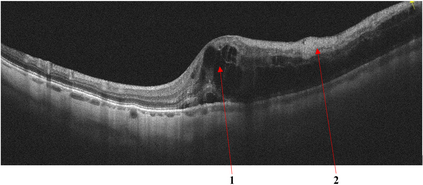

Optical coherence tomography (OCT) is a non-invasive imaging technique with extensive clinical applications in ophthalmology. OCT enables the visualization of the retinal layers, playing a vital role in the early detection and monitoring of retinal diseases. OCT uses the principle of light wave interference to create detailed images of the retinal microstructures, making it a valuable tool for diagnosing ocular conditions. This work presents an open-access OCT dataset (OCTDL) comprising over 1600 high-resolution OCT images labeled according to disease group and retinal pathology. The dataset consists of OCT records of patients with Age-related Macular Degeneration (AMD), Diabetic Macular Edema (DME), Epiretinal Membrane (ERM), Retinal Artery Occlusion (RAO), Retinal Vein Occlusion (RVO), and Vitreomacular Interface Disease (VID). The images were acquired with an Optovue Avanti RTVue XR using raster scanning protocols with dynamic scan length and image resolution. Each retinal b-scan was acquired by centering on the fovea and interpreted and cataloged by an experienced retinal specialist. In this work, we applied Deep Learning classification techniques to this new open-access dataset.